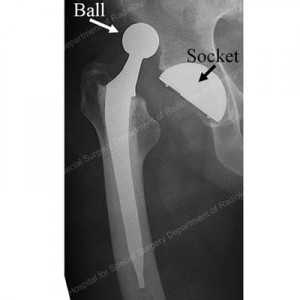

Implants for revision hip surgery

The implants used for the revision operation are broadly similiar to the ones used for first time sugery. They consist of a cup section inserted into the natural socket of the pelvis and a stem with a ball at its top aspect that is inserted into the femur bone. When the two are put together, a joint results much as is the case in nature where the ball at the top end of the thigh bone forms a joint with the hollow socket of the pelvis bone.

Femoral Revision: With regards to the revising or redoing the femoral component, there are two broad trends. One is to rebuild the damage in the femur (thigh bone) with bone graft. This technique is called impaction grafting. The femoral component which is much like the one used in primary surgery, is then cemented into the grafted bone.

The other broad trend is to use modular components without cement. Surgeons proficient with both techniques have obtained good results though the impaction grafting procedure has been around for longer than the modern modular components for use without cement (the cementless components). As the risks of disease transmission with bank transplant material have become well known and as the legislation for running the banks and using donated bone has become more complex, surgeons are not using impaction grafting as frequently as was the case only a few years ago. The components used without cement are supplied in a “knocked down” state which is very handy as it allows the surgeon to “make” an implant by putting together the components at the time of surgery. This mean that the implant can be “fabricated” in the operation theatre taking into account the best fit and suitability for the patient. Often the surgeon will have a wide choice of components or parts to put together in each section of the implant for maximum flexibility.

Impaction grafting: Impaction grafting is a technique used in revison surgery that has been devised to deal with loss of bone stock in the femur (thigh bone). The technique relies on first recreating a stable and rigid upper femur in cases with severe bone loss, using wires, wire meshes, donated bone or metal plates. In some cases all of these may be required. Once the outline “scaffold” or containment is created, donated or bank cancellous bone is inserted into the femoral tube. The bone graft is hammered into the tube recreated previously using specially shaped tamps that follow closely, the shape of the femoral component to be implanted. By this means a “new” tube is made from the bone graft material reinforced as neccessary with the metal work mentioned above. It may be difficult to believe that a bony tube made in this manner will be strong enough to take an implant, but the method does work. Once this stage of the operation is over, the surgeon will have made up the bony deficiency in the femur with the graft material and will have a bony tube with a cavity within to take the femoral component. The implant is then cemented into the cavity within the recreated femur

Modular Femoral Implants:

Modularity, as it applies to the hip replacement implants, refers to the availability of the components in sections or parts, rather than as a single piece – the monobloc version. Historically, hip replacments were available as two “bits” – one was meant for insertion into the natural socket and the other, into the femur bone. Fairly good results were obtained by these components, particuarly with respect to long term survival. However, the philosophy was very nearly “one size fits all”. This posed some practical problems by reducing the flexibility of the surgeon during the operation. For example, once the socket had been cemented in, there was no easy way to salvage the situation if the position or orientation was unsatisfactory. Similiarly, on the femoral side, once the component had been implanted, it was difficult to adjust soft tissue tension, or the length of the leg if that was neccessary.

The modular components changed this. On the socket side, the surgeon now had available to him, a metal shell that he could implant into the natural socket but still retain the ability to change the inside diameter of the bearing, it’s alignment and also introduce protection against dislocation if neccessary without having to “uproot” the socket component. On the femoral side, he could change the length of the ball to adjust soft tissue tension and leg length, after fixing the component into the femur. He was able to do this, because the ball was now available in lengths with female tapers that could be “cold welded” to the male taper on the top end of the femoral component.

With time, there were further developments in modularity, which is particularly handy for revision cases or the difficult and challenging primary (first time) hip replacement procedures such as in patients who have deformities in the hip joint due to abnormal development.. The current components allow the surgeon to choose not only the size and length of the ball at the final stage of the surgery, but also the length of the stem section, its shape, surface finish and curvature, the shape and size of the upper end of the femoral component, the degree of offset and the rotation or twist of the upper section of the implant in relation to the stem section as well as the surface finish of this section. The advantage with these type of components is that the final implant can be assembled in the patient (or outside prior to implantation) to closely match the patient’s requirements. This in turn enables better soft tissue tension, stability, leg length equalisation, muscle function and reliability.